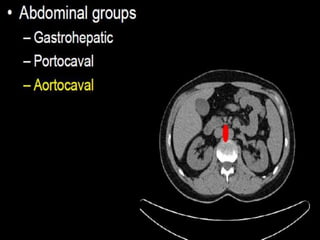

CT cross sectional anatomy.